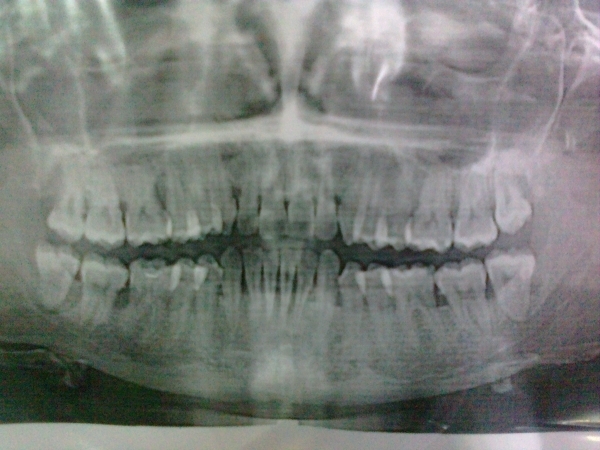

Мне 29 лет. Ставят сильнейший пародонтоз. Прогрессирует разрушение костной ткани, шатается верхняя 5-ка справа и по-моему нижняя тоже. Десны уже не просто кровоточат, а вздуваются в разных местах, как воздушные шарики. Вчера вскрывали флюс. Даже на открытый кюретаж, который отправили сделать, не могу пойти, т.к. десна в нестабильном состоянии, при этом анализы (гормоны, кальций, сахар) все в норме. Сказали кроме кюретажа, необходимо сначала депульпирование нижних зубов, иначе потеряю их. И депульпировать те зубы, которые шатаются (5-ка нижняя и верхняя справа) + шинирование и уколы в десны.